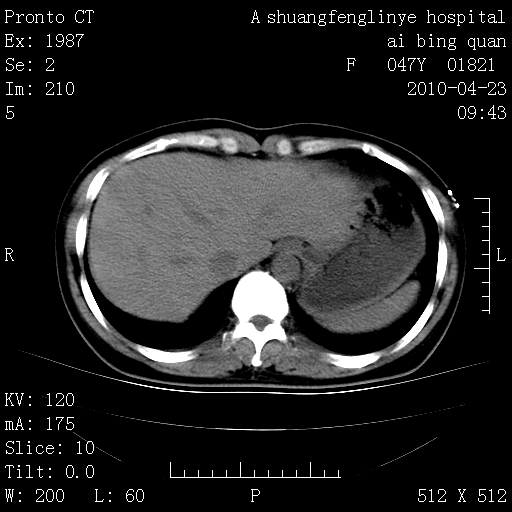

标题: CT25944:胸痛、气短、前几日高烧!肺Ca?请会诊! [打印本页]

标题: CT25944:胸痛、气短、前几日高烧!肺Ca?请会诊!

kaolv 周围型肺癌并同肺转移

双肺多发结节,考虑转移瘤,肺癌肺转移不除外

周围型肺癌并肺转移

双肺多发结节,部分密度较高,最大结节边缘光滑。临床有“胸痛、气短、前几日高烧”病史。首选考虑:右肺感染性病变!建议积极消炎后复查!